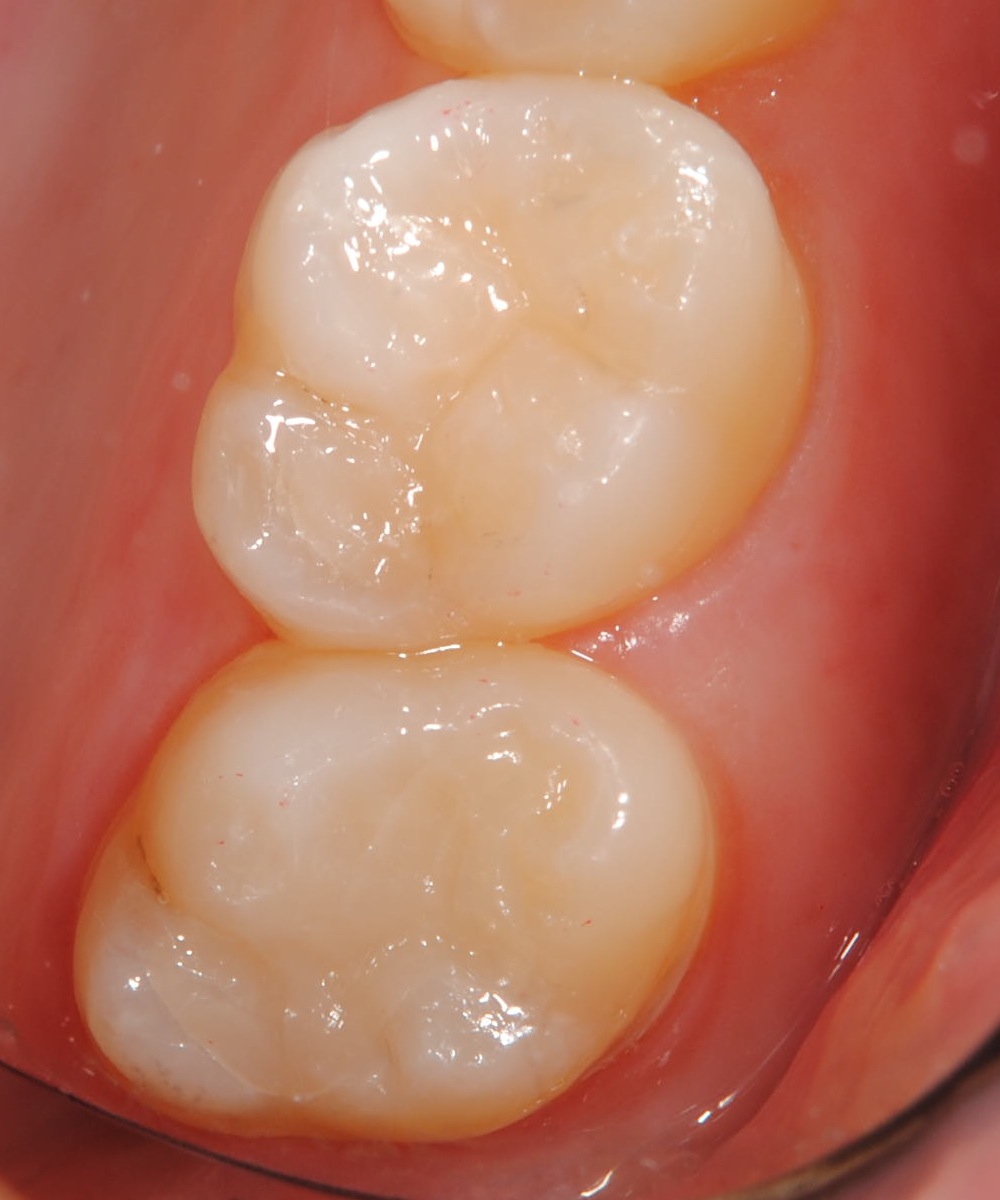

先日、従業員の口腔内診査を行った所、15年くらい前にセットした金属(インレー)と歯の境目に段差が生じていました。レントゲン診査では2次齲蝕の可能性がありましたが外してみて意外と虫歯が進行していて本人もびっくりしていました、虫歯を除去した後はコンポジットレジンで修復を行いました。

近年コンポジットレジンの材質が改良され噛み合わせの力がかかる部位への応用範囲が広がってきました。審美性、耐久性などセラミックには劣りますが、見た目もきれいですし(吸水性があるので長期使用で着色します)多くの場合1日で診療が終わります、噛み合わせや残存歯質の状態によっては適応できない場合もありますのでご相談下さい。治療は健康保険の適応内です。